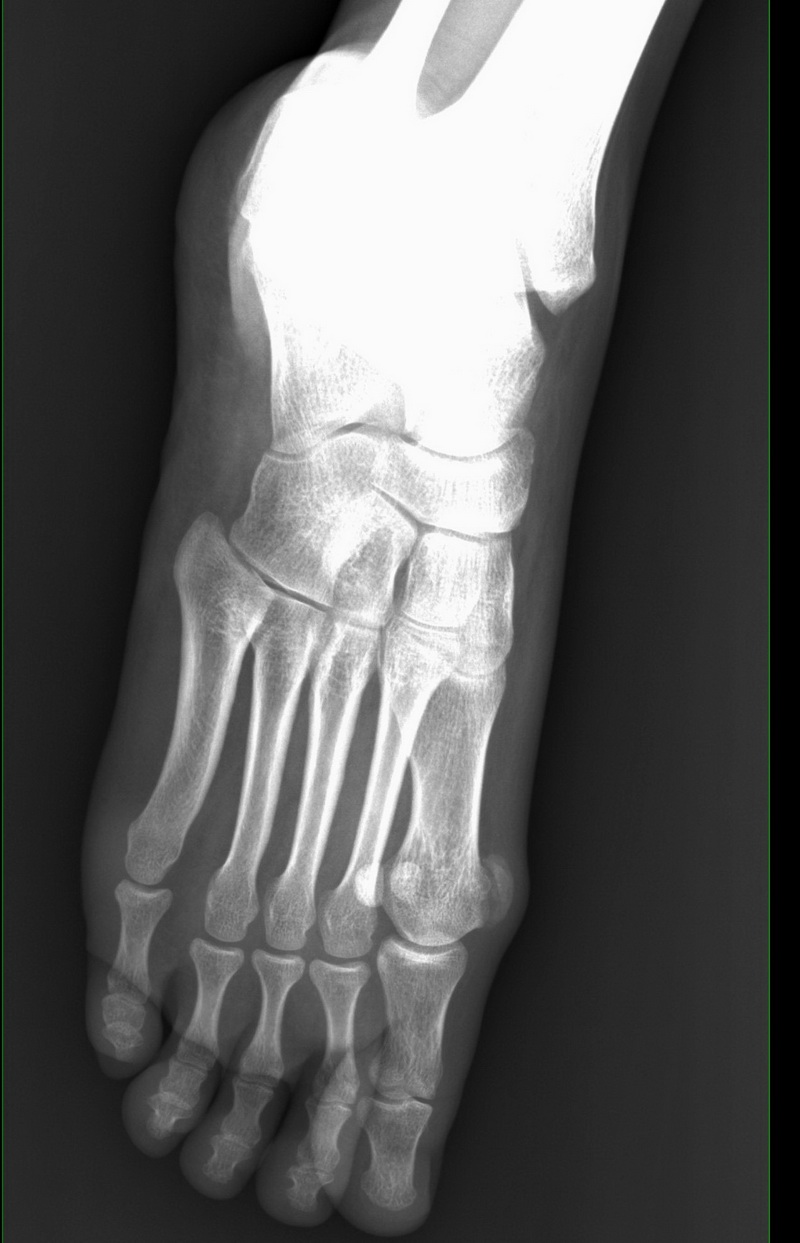

跖趾关节半脱位

跖趾关节脱位10个月疫情耽误了